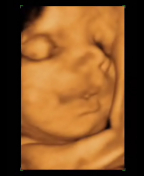

Nuestra guía del embarazo, escrita por el Dr. Miguel Ángel Herráiz, te ayuda a saber todo lo que pasa cada mes de la gestación: cómo cambian madre a hijo, las pruebas diagnósticas que tienes que realizar, las curiosidades de cada etapa… Vemos al bebé crecer dentro del útero materno a través de interesantes ecografías.